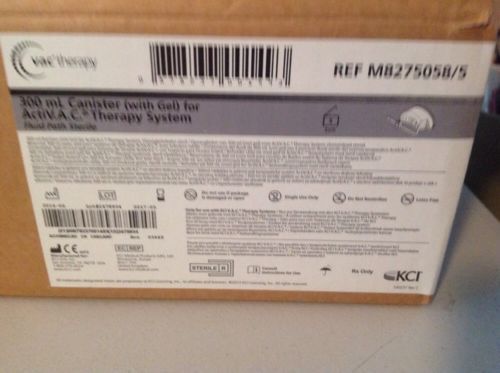

kci wound vac - I Have (4) 300ml Canisters For ActiV.A.C. Therapy System